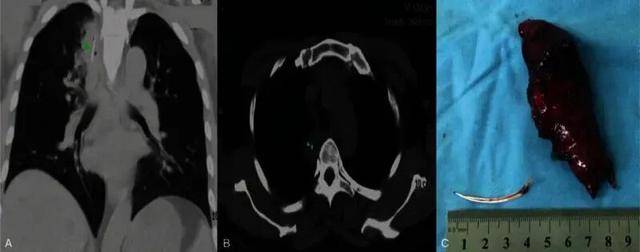

在极少数情况下,鱼刺甚至可能因为反复的错误尝试穿透食管进入胸腔或肺部。一例病例报道显示,患者在误吞鱼刺后出现肺部脓肿,最终需要胸腔镜手术取出异物[5]。

A图和B图为一根长4厘米的鱼刺嵌在右肺上叶的脓肿中。C图为鱼刺和肺脓肿的合影。图源:参考资料